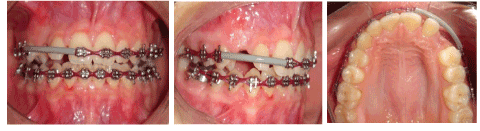

0.022 slot Roth brackets had been bonded on all upper and lower teeth except #12 which acted as a free body initially till the canine had been moved away from its root (Figure 3). After 6 months of alignment, space started to be created for the canine using opening coil spring (0.010 x 0.035 inch) (Figure 4). The first stage of surgery was planned to be VISTA technique in order to move the canine horizontally and to situate the canine crown directly under its socket using the microimplant (MI) (Figures 5 and 6). During surgery, all the bone distal to the canine crown till its CEJ which is in the way of its movement had been removed. A microimplant from (Ormco) VectorTas of 2 x 8 mm had been placed in the infrazygomatic crest parallel to the upper right first molar (Figure 7). A lingual button bonded on the labial surface of the canine and connected to the microimplant via a power chain which was passing under the alveolar mucosa over the canine. The horizontal movement of the crown had been activated every month by cutting a hole from the power chain. A panoramic periapical radiograph A-B taken directly after MI placement and 3 months over that to control the movement of the canine (Figures 8 and 9). After 3 months of horizontal movement of the canine, the patient referred again for the 2nd stage of surgery where a full reflected flap performed in order to remove the old power chain and place new one which is directly connected to the main archwire (Figure 10). All the bone above the canine crown till the 2 mm from the alveolar crest had been removed in order to facilitate the tooth movement vertically. The main arch wire which is 0.017x0.025 Stst had been offset in the area between #12, 14 (Figure 11). This offset placed to help for keeping the canine root in the alveolar bone and avoid the labial tipping of the crown. A crimpable attachment with a hook fixed on the wire directly over the canine crown and a power chain connected directly from the lingual button to the hook (Figure 12). The vertical movement of the crown had been activated every month by cutting a hole from the power chain. After the canine came out of the soft tissue a bracket bonded and thin wire placed in its slot with a sequence of 0.12 Niti, 0.14 Niti, 0.16 Niti, 0.16 x 0.22 Niti, 0.16 x 0.22 Stst, 0.17 x 0.25 Niti and 0.17 x 0.25 Stst. Canine root torque had been checked after its reaching to the occlusal plane and found that no need for any adjustment since it is similar with the opposing canine root eminence (Figure 13). After 24 months of active treatment, all appliances were debonded (Figure 14). Orthopantogram, lateral cephalography and periapical radiograph had been taken to record as a baseline for future follow up and assessment. Clear overlays delivered for both arches as retainers with proper instructions (Figure 15).

Figure 11. Intra oral photos show the vertical traction #13

Figure 12. Intra oral photos with a button which attached on the canine to be shown through the soft tissue as #13 started to erupt

Figure 13. Bracket bonded on #13 after its eruption and starting with its levelling and alignment